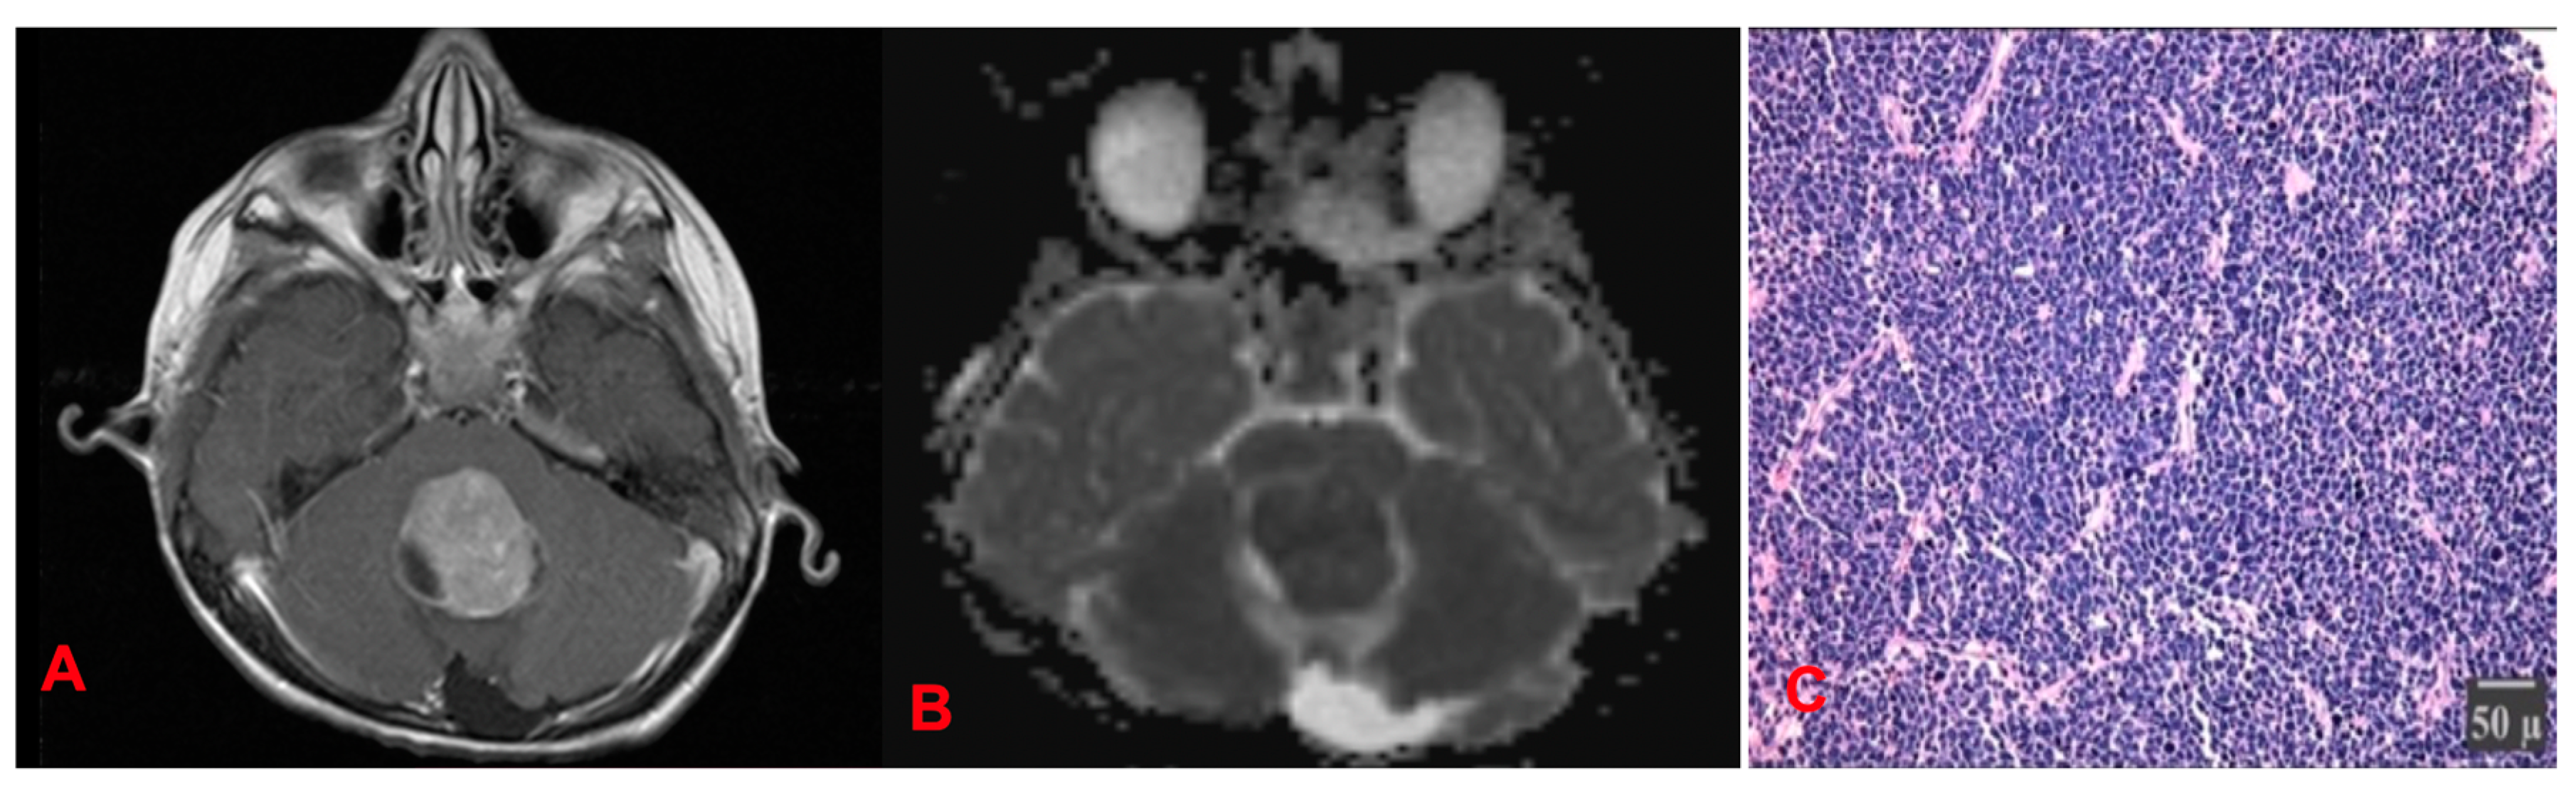

4.1.3. Medulloblastomas (MB) (Figure 17)